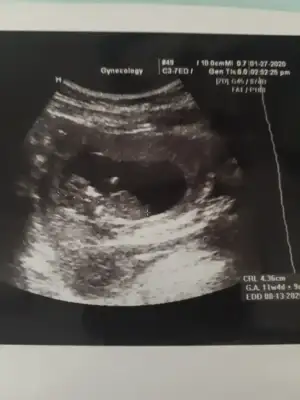

Kızçelet merhaba ☺️ Aşırı rica etsem de benim bebişimi de yorumlasanız olur mu doğum ağustosta inşAllah çin takvimi vs. Herşey de erkek çıktı içime de erkek doğuyor ama sağlıklı olsun tabi kız istiyoruz ☺️ Nub teorisine göre sanki kız gibi geldi bana bilen ilgilenen yorum yaparsa çok dua ederim ona 🥰🥰🥰

• A7191D7F-F9F6-4E86-BC5A-9F422ECC0F60.webp

A7191D7F-F9F6-4E86-BC5A-9F422ECC0F60.webp

21,9 KB · Görüntüleme: 57

Kızçelet merhaba ☺ Aşırı rica etsem de benim bebişimi de yorumlasanız olur mu doğum ağustosta inşAllah çin takvimi vs. Herşey de erkek çıktı içime de erkek doğuyor ama sağlıklı olsun tabi kız istiyoruz ☺ Nub teorisine göre sanki kız gibi geldi bana bilen ilgilenen yorum yaparsa çok dua ederim ona 🥰🥰🥰

Net degil usg erkek gibi gibi diye ekliyorum 12 + usgde paylaşırsınız netleştirelim yada varsa başka usg paylaşın